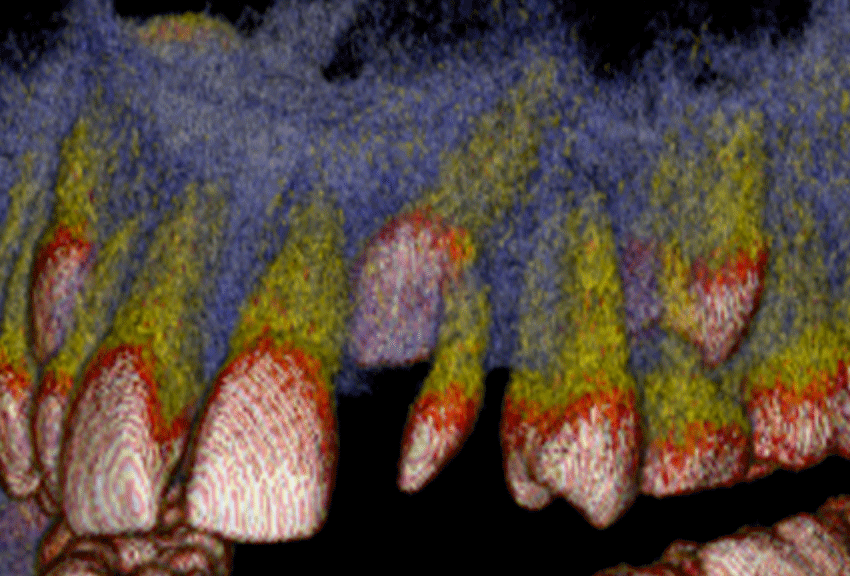

cone beam CT

The patient is seated in the chair. The machine rotates around the head & emits a collimated cone-shaped x-ray beam. The scan takes 9.6 seconds. 512 computer files are generated. With special software, it is possible to create any number of views from any angle in both 2D and 3D. The examples below show some of the possibilities of this technology.

impaction